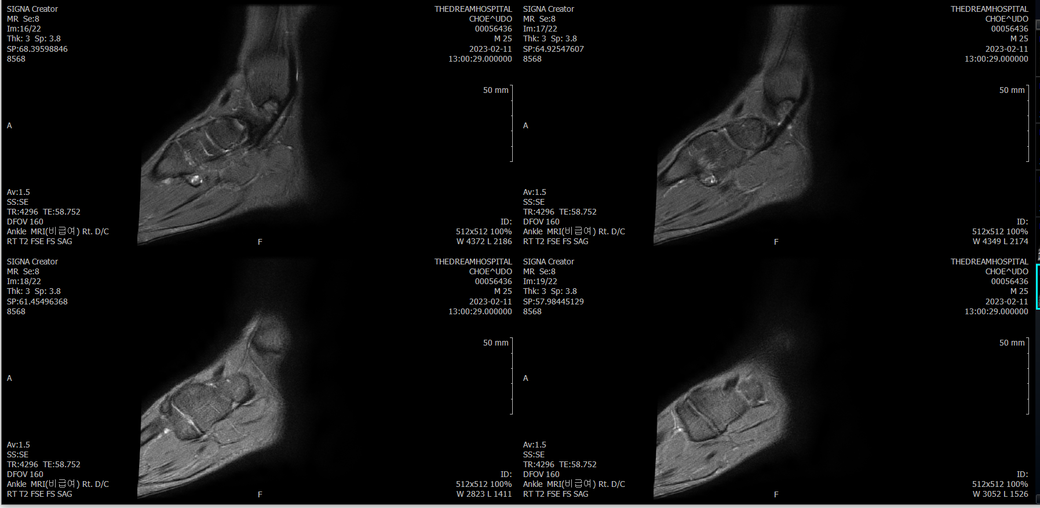

오른발목 mri 전체사진입니다. 제가 병원을 갈수없는상황인지라.... 봐주시면 감사하겠습니다.

엑스레이에서는 문제가 없다고 하여 오른발목 mri촬영했습니다.

우선 전반적으로 봤을 때 큰 이상은 없어보입니다.

전거비인대 등도 저명한 손상은 없는 것 같아 보이지만, 어느 부분의 통증 등으로 인해 촬영을 하셨는지 말씀을 해주신다면 보다 정확한 병변파악이 가능하겠으며, 병원에서 판독이 완료되신다면 전화 등으로 문의를 해보시는 것이 좋겠습니다.